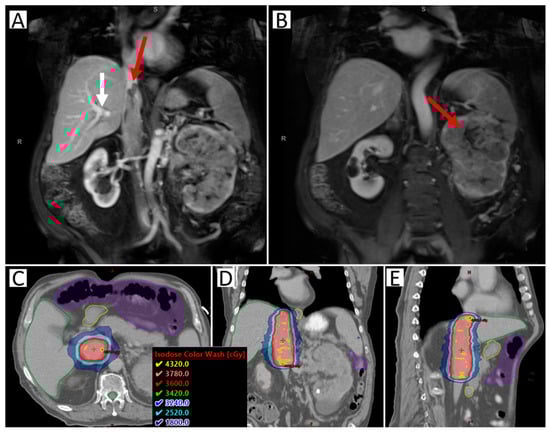

- Hannan, R.; Margulis, V.; Chun, S.G.; Cannon, N.; Kim, D.W.N.; Abdulrahman, R.E.; Sagalowsky, A.; Pedrosa, I.; Choy, H.; Brugarolas, J.; et al. Stereotactic radiation therapy of renal cancer inferior vena cava tumor thrombus. Cancer Biol. Ther. 2015, 16, 657–661. [Google Scholar] [CrossRef] [PubMed]

- Freifeld, Y.; Pedrosa, I.; Mclaughlin, M.; Correa, R.M.; Louie, A.V.; Maldonado, J.A.; Tang, C.; Kadow, B.; Kutikov, A.; Uzzo, R.G.; et al. Stereotactic ablative radiation therapy for renal cell carcinoma with inferior vena cava tumor thrombus. Urol. Oncol. Semin. Orig. Investig. 2022, 40, 166.e9–166.e13. [Google Scholar] [CrossRef] [PubMed]

- Margulis, V.; Freifeld, Y.; Pop, L.M.; Manna, S.; Kapur, P.; Pedrosa, I.; Christie, A.; Mohamad, O.; Mannala, S.; Singla, N.; et al. Neoadjuvant SABR for Renal Cell Carcinoma Inferior Vena Cava Tumor Thrombus—Safety Lead-in Results of a Phase 2 Trial. Int. J. Radiat. Oncol. 2021, 110, 1135–1142. [Google Scholar] [CrossRef]